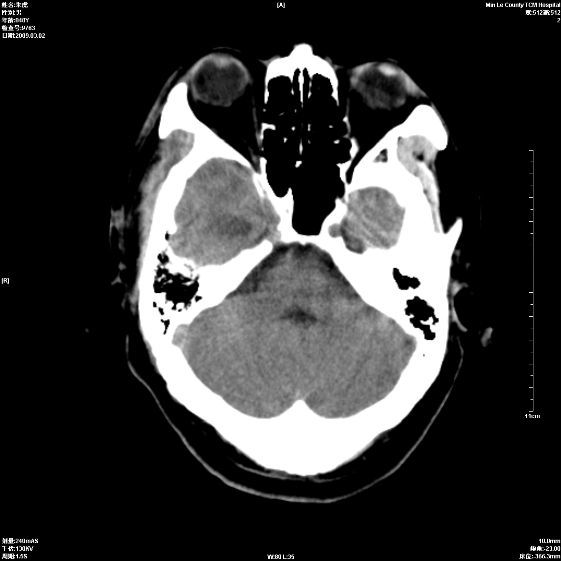

标题: CT18444:男颅咽瘤术后一月复查脑积水增多 [打印本页]

标题: CT18444:男颅咽瘤术后一月复查脑积水增多

右侧额叶局软化灶,梗阻性脑积水。

右额叶软化灶。梗阻性脑积水。

手术后改变

1、右额叶脑软化

2、脑积水

四脑室上方积水,右额叶软化灶。

1)右侧额颞部颅骨术后改变。2)右侧额颞叶脑软化灶。3)脑积水(梗阻性)。

手术后改变1、右额叶脑软化2、梗阻性脑积水。